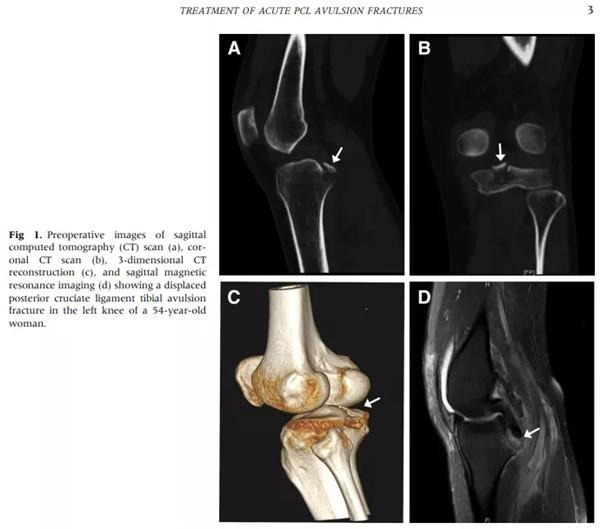

近日,关节镜领域顶级杂志——美国《Arthroscopy(关节镜)》在线发表了徐州医科大学附属医院骨科《Results of Arthroscopic Treatment of Acute Posterior Cruciate Ligament Avulsion Fractures With Suspensory Fixation(关节镜下悬吊固定治疗急性后交叉韧带撕脱性骨折的结果)》的临床手术技术论文,影响因子4.433。本论文由徐州医科大学附属医院骨科郑伟副主任医师、潘彬主治医师、周冰主任医师及研究生侯万星等合作完成。

本研究旨在通过悬吊技术评估关节镜治疗急性后交叉韧带(PCL)撕脱性骨折的临床效果。目前,Pubmed检索该手术类似技术国际报道仅有6篇文献,共计10余例病例,而医院应用该技术已累计完成后交叉韧带撕脱性骨折的手术40余例。